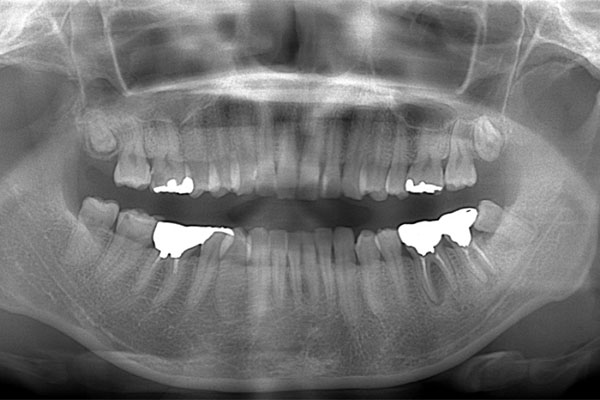

患者様の初診時レントゲン写真

【担当医師所見】

左下奥歯は親知らずが原因でクラウン(かぶせ物)の下まで虫歯になっています。 またその手前の歯は根中央部に大きな透過像(黒い像)が見られます。クラウン除去後、マイクロスコープ下で確認したところ中央部は亀裂が入り保存不可能な状態になっており抜歯となりました。

また右上6番にも大きな透過像があり虫歯となっていることがわかります。